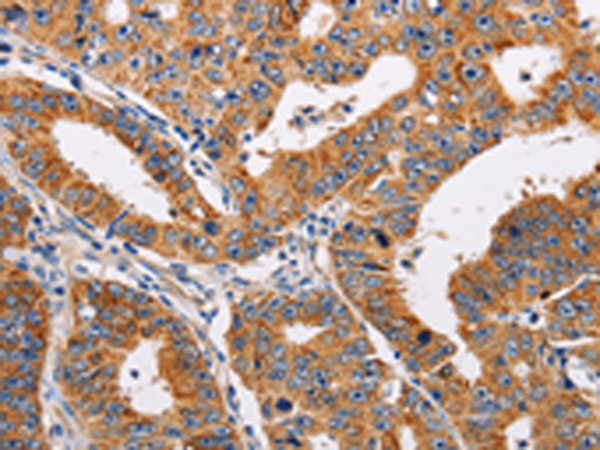

分类: 科研抗体货号: P00872别名: AG3; AG-3; HAG3; hAG-3; BCMP11; PDIA18应用: WB,IHC反应种属: Human, Mouse